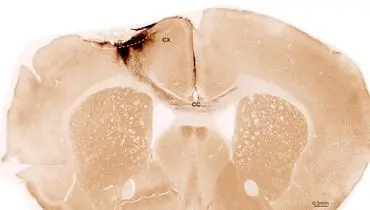

درمان با سلولهای بنیادی توانست آسیبهای ناشی از سکته مغزی را در موشها معکوس کند، نورونها را بازسازی کرده و حرکت را…